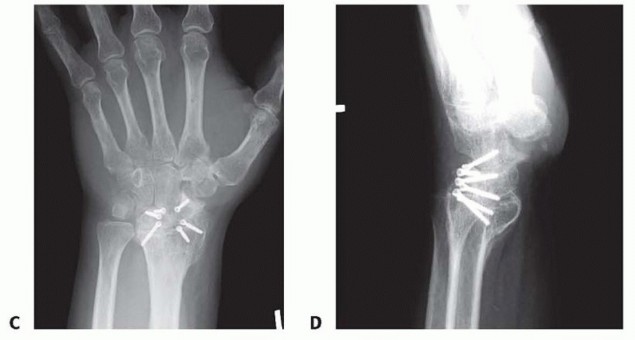

TECH FIG 6 • A,B. Preoperative AP and lateral radiographs. C,D. Postoperative AP and lateral radiographs following radiocarpal arthrodesis. Under fluoroscopy, correct any preoperative VISI or DISI deformity.A Kirschner wire inserted into the dorsal lunate may be used as a joystick to effect correction.Stabilize the lunate in the reduced position with provisional Kirschner wires from the radius into the lunate.Harvest bone graft from the distal radius or iliac crest and pack the graft tightly into the palmar radiolunate joint.Secure the lunate to the radius with Kirschner wires, headless screws, staples, or small blade plates. Pack the remaining bone graft into the dorsal radiolunate joint.Perform a routine closure and apply a splint.The previously described technique is taken from published data.14,278. Capitolunate ArthrodesisMake a dorsal incision from base of second metacarpal to Lister tubercle.Use the third and fourth extensor interval as described earlier.Perform an inverted “T” capsulotomy to visualize the scapholunate and capitolunate joints. Perform a limited styloidectomy (˜3mm) and excise the proximal pole of scaphoid.Stabilize distal scaphoid to capitate with a Kirschner wire. Alternatively, the entire scaphoid can be excised.Denude the capitolunate articulation.Harvest bone graft from distal radius or iliac crest and pack it into this prepared joint.Tricortical iliac crest graft allows maintenance of carpal height.Assure capitolunate alignment with a Kirschner wire as described earlier for CHLT fusion.Place a guidewire followed by headless screw into proximal ulnar corner of lunate as described earlier for CHLT fusion.Take wrist through a range of motion to be certain a mechanical block is not present. Perform a standard closure and apply a splint.The previously described technique is taken from published data.12,15P.989